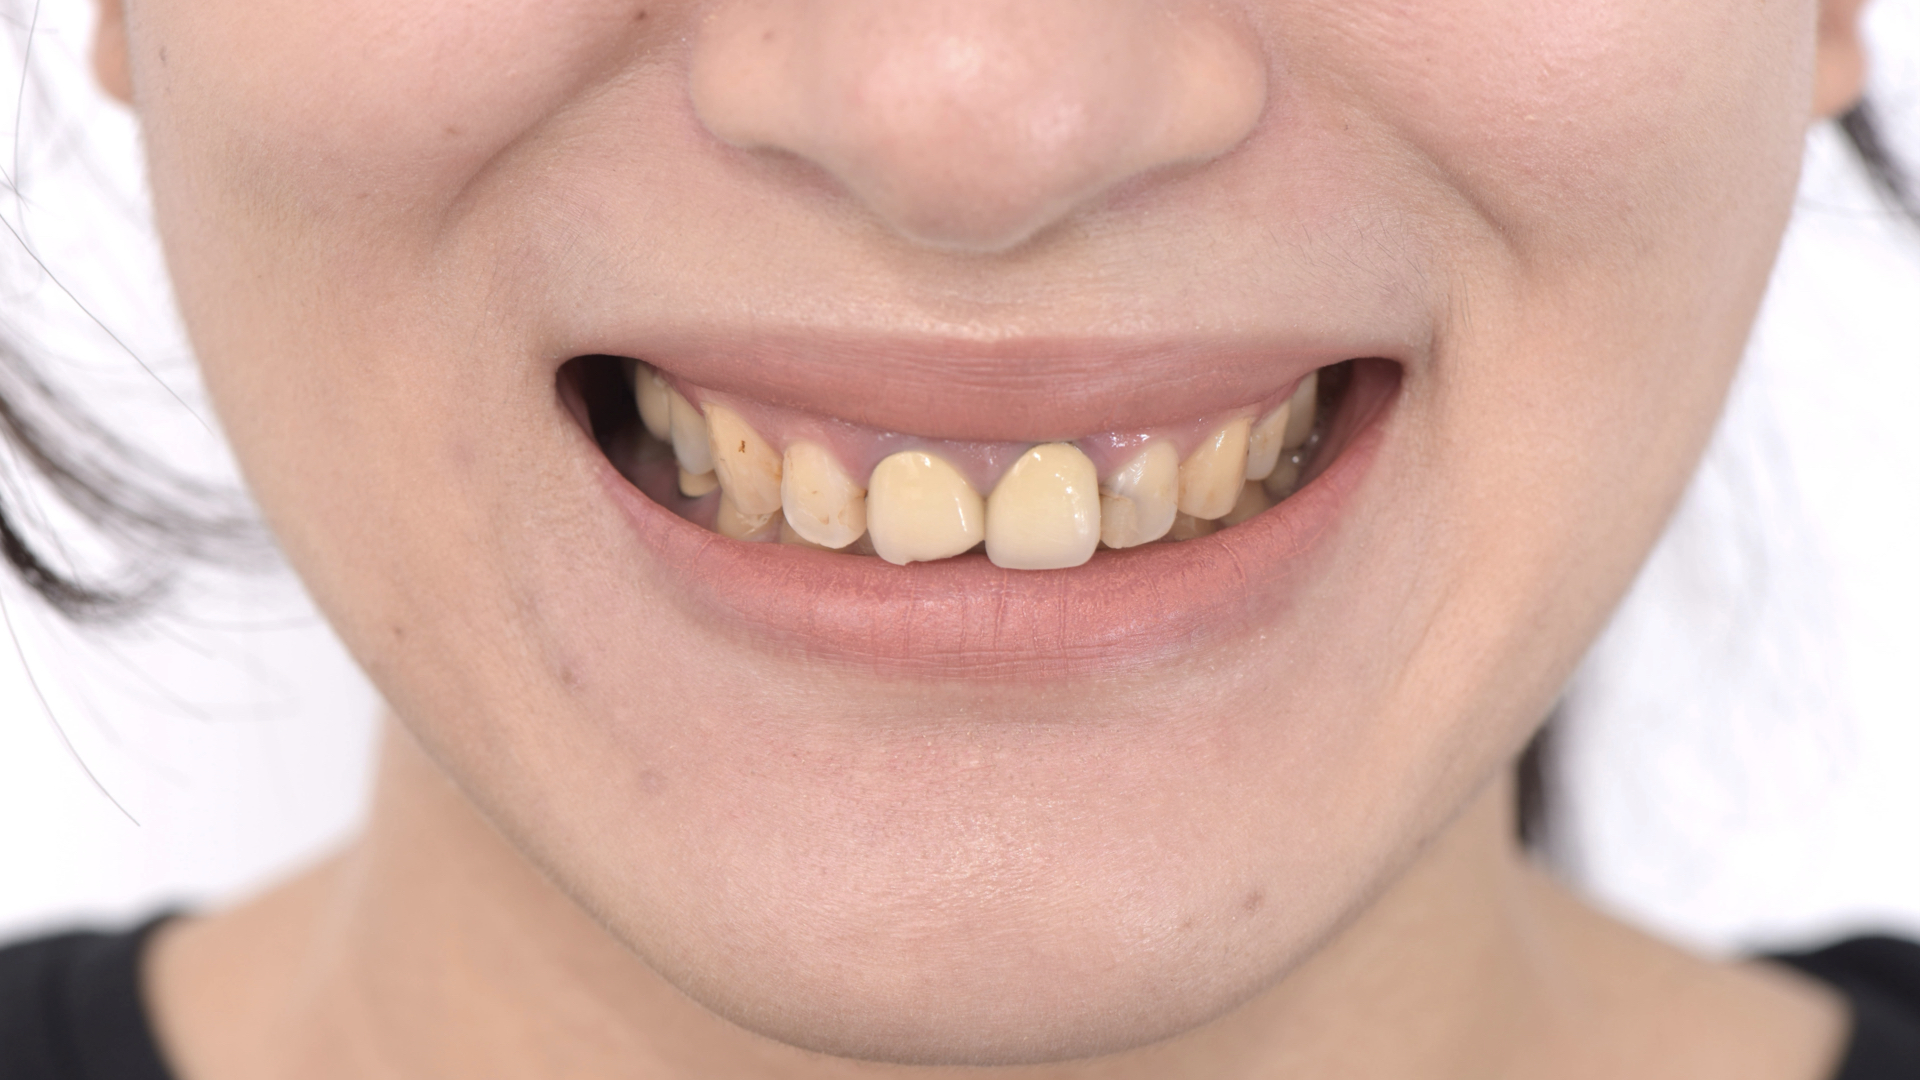

鄧小姐一直覺得笑容不是很滿意,以前的舊假牙邊緣開始黑黑的,加上前陣子因為咬到硬物,邊緣陶瓷裂了一角,更加加深對門牙的在意程度,搞得自己都不敢笑了。

假牙破裂,邊緣有黑色邊

右邊中門牙牙齦腫起來